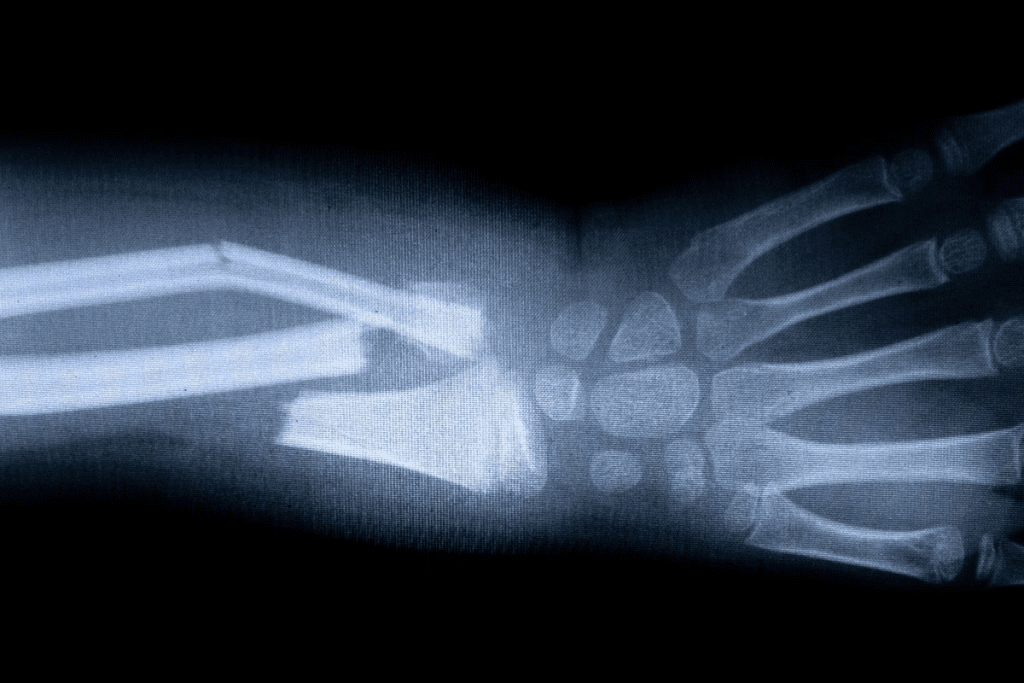

Why Bone Scans Can Detect Cancer Earlier Than X-rays

Bone scans are great at spotting changes in bone activity. They find cancer before X-rays can. This is because they use a special tracer that shows up in active bones.

Early detection is vital for better treatment. Bone scans are a big plus because they catch cancer early.

Limitations: When Bone Scans May Miss or Misidentify Cancer

Even though bone scans are good, they’re not perfect. They can find problems but not always say it’s cancer. Things like arthritis or broken bones can also show up as positive.